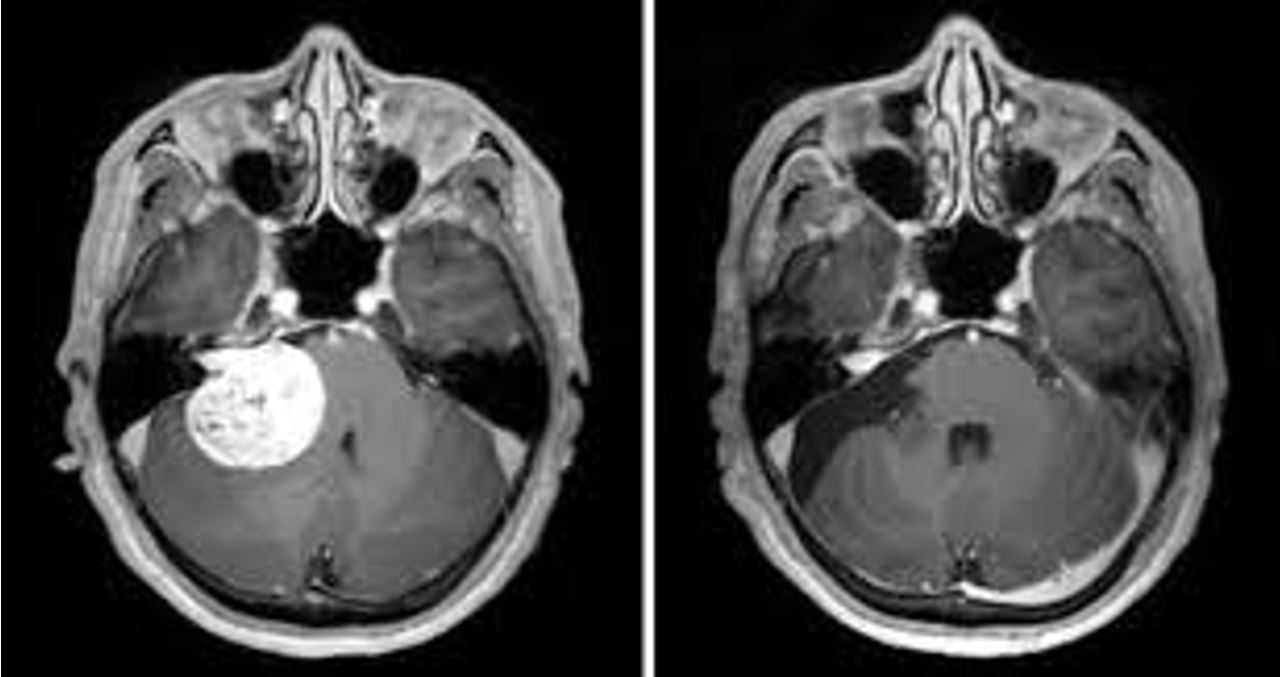

Chẩn đoán xác định dựa vào các phim chụp cắt lớp vi tính hoặc cộng hưởng từ. Các phim cộng hưởng từ có tiêm thuốc đối quang từ được coi là phương tiện chẩn đoán chính xác nhất đối với u dây thần kinh VIII. U thường có đặc điểm hình tròn bầu hình bầu dục nằm ở ống tai trong lan vào vùng góc cầu tiểu gây chèn ép cầu não và tiểu não. Mật độ u có thể thuần nhất, hoặc dạng nang và đặc xen kẽ. Phim chụp cắt lớp vi tính giúp khảo sát những thay đổi vùng ống tai trong liên quan đến tế bào xoang chũm, trên cơ sở đó giúp hoạch định kế hoạch mổ, đặc biệt là mổ theo đường xuyên mê nhĩ.

Hình 2. Hình ảnh cộng hưởng từ u dây thần kinh VIII